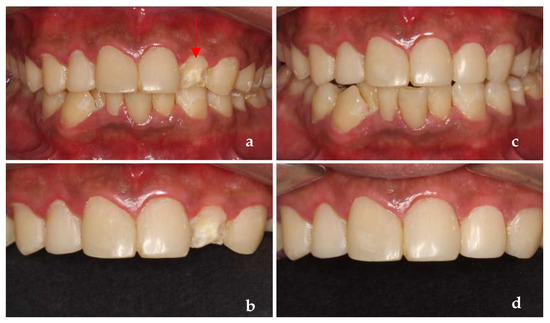

A 26-year-old male patient came to our clinic because of spontaneous pain in his right posterior tooth for one week. The patient had no systemic disease, and the family history showed no abnormalities. He described his job as a waiter with no exposure to acid substances. However, he loves to drink Coca-Cola and drinks more than 1 L of Coca-Cola every day; he also loves snacks and brushes his teeth less than once a day. These are the main causes of his dental caries. Dental examination found that the patient had poor dental hygiene with I-II° calculus supragingival and subgingival. All his teeth had extensive caries on the cervical region of the buccal and labial surfaces. The caries of teeth #14–24 even invades the tooth cusps. No lesions were found in the palatal and lingual surface. The pulpal surfaces of erosive lesions contained brown-colored, leathery, carious dentin. None of the pulp cavities were involved and the teeth remained asymptomatic on percussion, palpation and cold testing, except for tooth #46. The patient’s toothache came from tooth #46. There were two visible holes in teeth 46 buccal and occlusal surface, the perforation could be detected in the buccal surface, and the probing pain was obvious. There was no pain on percussion but severe pain on cold testing and heat testing (Figure 2a–d).

Figure 2.

(a) The photograph of the patient at first visit; (b) Upper teeth; (c) Lower teeth; (d) Panoramic X-ray of the patient (after the root canal therapy of teeth 46).